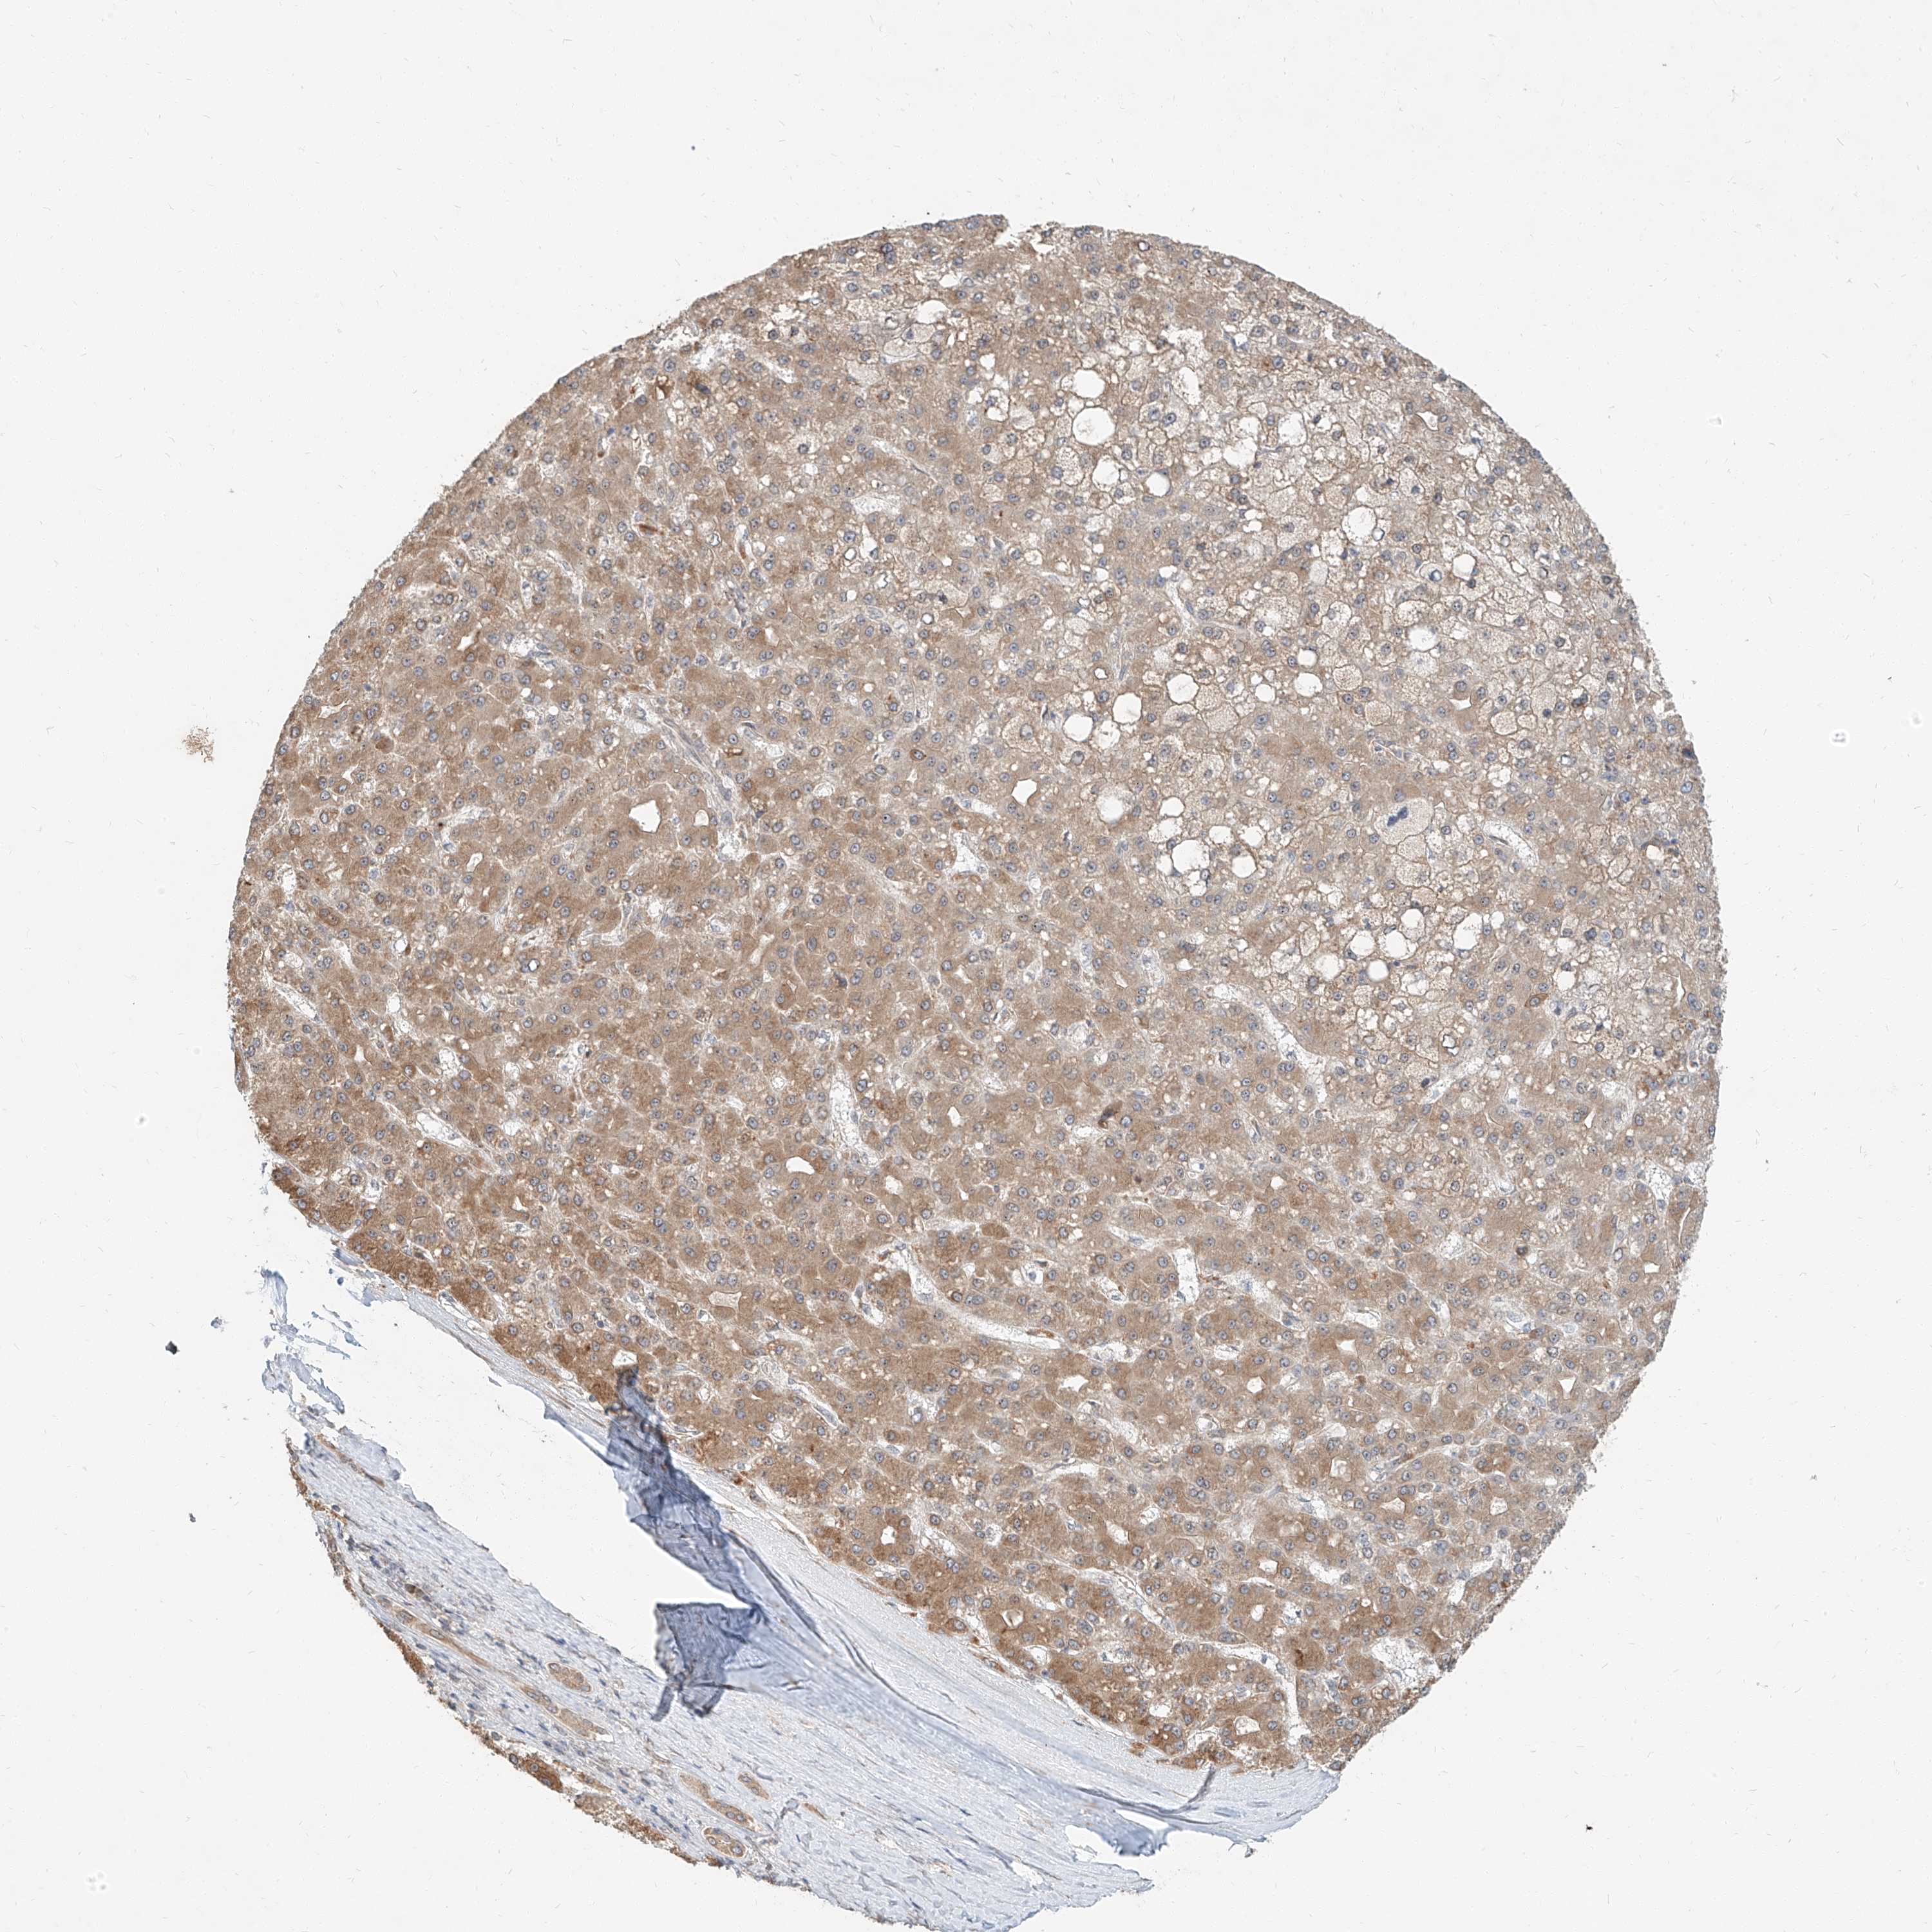

LIVER CANCER - Protein expressioni

A mouse-over function shows sample information and annotation data. Click on an image to view it in a full screen mode. Samples can be filtered based on level of antibody staining by selecting one or several of the following categories: high, medium, low and not detected. The assay and annotation is described here.

Note that samples used for immunohistochemistry by the Human Protein Atlas do not correspond to samples in the TCGA dataset.

Antibody stainingi

Antibody staining in the annotated cell types in the current human tissue is reported as not detected, low, medium, or high, based on conventional immunohistochemistry profiling in selected tissues. This score is based on the combination of the staining intensity and fraction of stained cells.

Each image is clickable and will lead to virtual microscopy that enables deeper exploration of all samples and also displays staining intensity scores, fraction scores and subcellular localization as well as patient and tissue information for each sample.

Antibody HPA030604

Staining

High

Medium

Low

Not detected

Intensity

Strong

Moderate

Weak

Negative

Quantity

>75%

75%-25%

<25%

None

Location

Nuclear

Cytoplasmic/membranous

Cytoplasmic/membranous,nuclear

Cholangiocarcinoma

Carcinoma, Hepatocellular, NOS